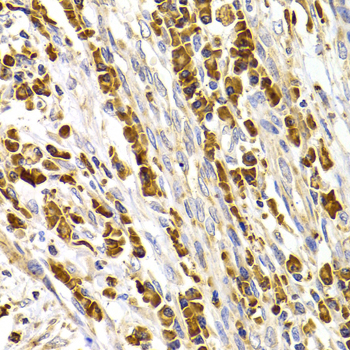

• A7220: image 2

Immunohistochemistry of paraffin-embedded human stomach cancer using TACR3 antibody at dilution of 1:100 (x400 lens).